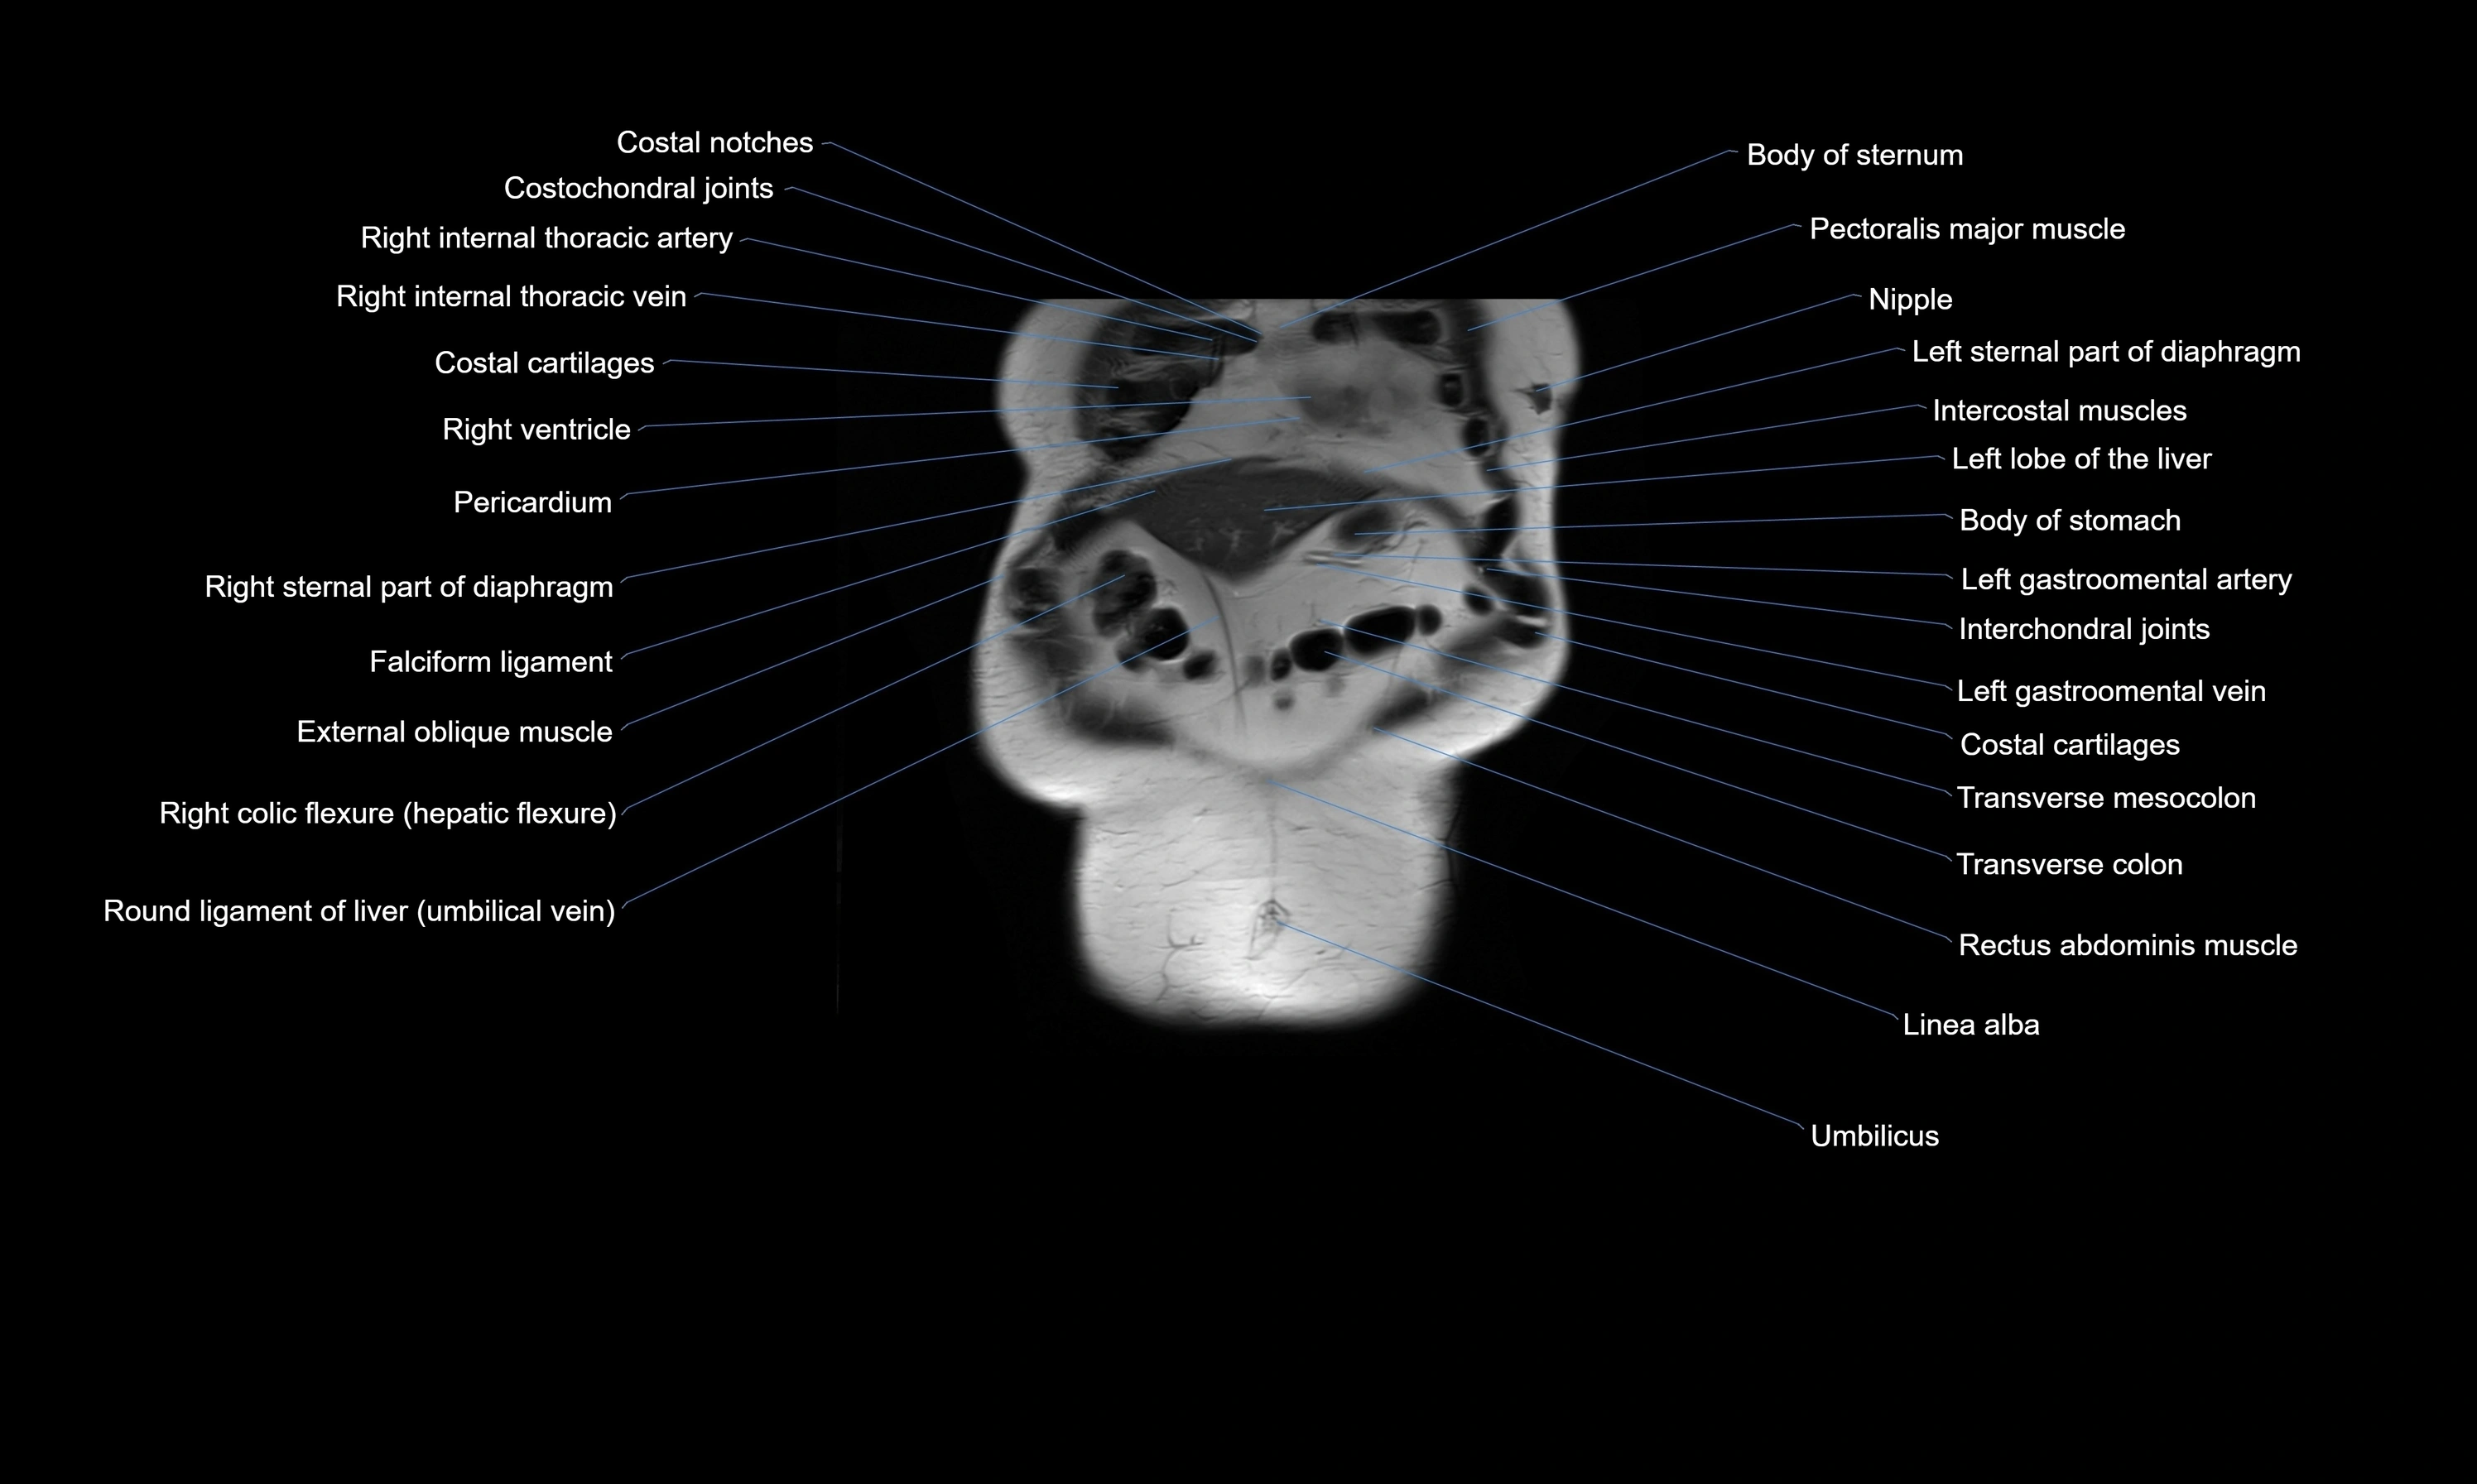

MRI images